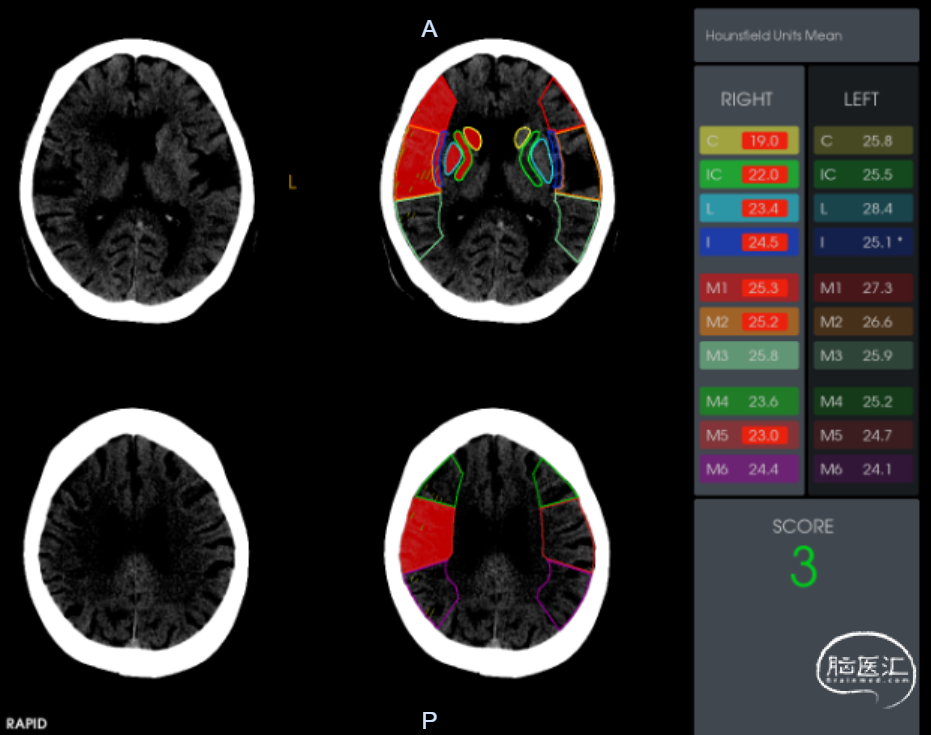

术前影像学检查

ASPECTS:3分

脑CT灌注:右侧额叶、颞叶、顶叶缺血低灌注;mismatch 155ml。